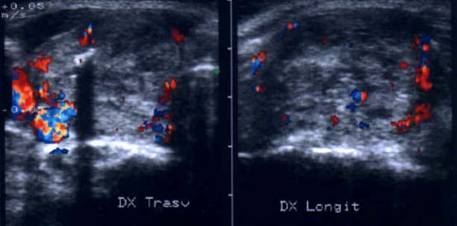

ecocolordoppler si powerdoppler- acelasi nodul

Vascularizatie interna, mai evidenta in powerdoppler.